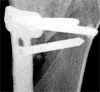

Montag, 19. September: Good News

Grauer Himmel, Bise, Kälte - doch die Röntgenkontrolle und Sprechstunde bei Prof. Stäubli verlief durchwegs positiv: Die Schrauben halten, die Stellung der Beine stimmt, die Gelenksachse stimmt. Nächste Kontrolle in drei Monaten - und in drei Wochen kann ich bereits die Krücken in die Ecke stellen. Das ist viel besser als erwartet.

Auch sonst ist fast alles in Butter: Schon seit zwei Wochen fühle ich, dass es möglich sein sollte, voll aufs operierte Bein zu stehen - erstaunlich für so einen komplexen Eingriff. Nun ists offiziell: Ab sofort kann ich daheim auch ohne Stöcke kurze Distanzen gehen. Medis nehme ich schon seit etwa zwei, drei Wochen keine mehr - auch das ist verglichen mit früheren Operationen erstaunlich. Strecken kann ich das Knie (zum ersten Mal seit dem Unfall im April 2001!) ganz, beugen bis etwa 110-120 Grad - in den letzten Wochen stieg dieser Wert fast täglich. Cool - alles durchwegs positiv also! Einzig ein kleiner Restschmerz im Osteotomiespalt ist noch vorhanden, dazu die üblichen kleinen Arthrose-Stiche im Knie. Bald gehts los mit deftiger Kräftigung, dann sollten die Muskeln auch schnell wieder zurück sein.

Die aktuellen Röntgenbilder (bitte klicken für grössere Fassungen):

Vergleich 15. August 2005 und 19. September 2005 von vorne

Vergleich 15. August 2005 und 19. September 2005 von der Seite